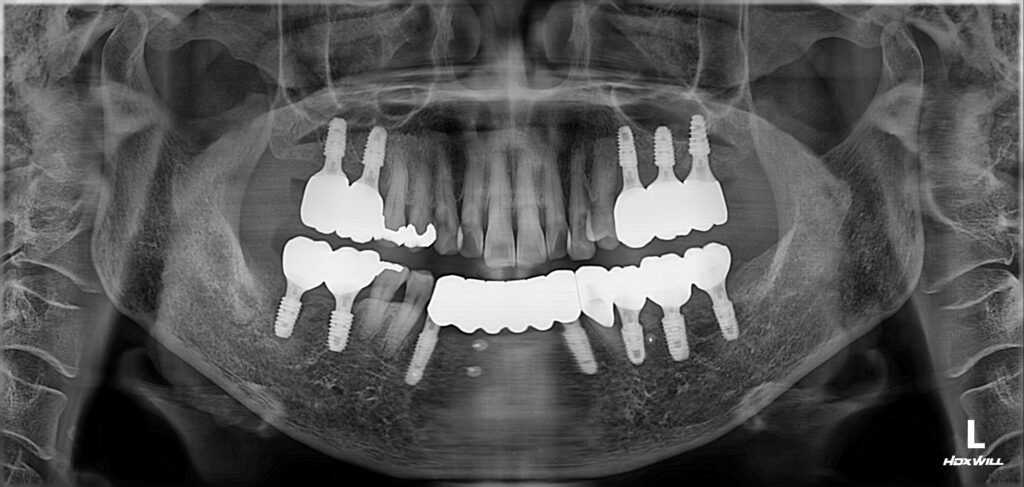

임플란트 골유착 및 보철 완성

수술 후 약 3개월간 골 유착(뼈와 임플란트가 붙는 과정) 기간을 기다렸습니다.

그 후 특수 장비를 이용해 골 유착 정도를 측정한 결과, 모든 부위에서 안정적인 수치가 확인되었습니다.

정밀하게 본을 뜬 뒤 최종 보철(치아머리)을 제작하여 치아 기능과 심미성을 회복시켜 드렸습니다.

처음 오셨을 때와 비교하면 윗니와 아랫니가 물리는 관계(교합관계)가 훨씬 안정적으로 개선되었습니다.

견고하게 식립된 임플란트가 어금니의 기능을 잘 회복해 주고 있고, 앞니 보철도 함께 정리하여 전체적인 기능 균형을 되찾았습니다.

어금니가 단단하게 버텨줘야 앞니도 제 역할을 할 수 있으며, 또한 앞니가 제 역할을 해줘야 어금니도 과도한 힘을 받는 것을 막을 수 있습니다.

이런 균형 있는 치료가 이루어져야 향후 잇몸과 치아 상태를 오래도록 안정적으로 유지할 수 있죠.